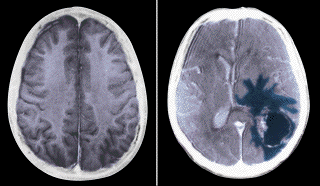

Eμβόλιο για τον καρκίνο του εγκεφάλου

Ένα πειραματικό εμβόλιο κατά του καρκίνου του εγκεφάλου έδωσε ικανοποιητικά και πολλά υποσχόμενα αποτελέσματα σε προκαταρκτικές μελέτες, στο ινστιτούτο Jonsson Cancer Center του Πανεπιστημίου UCLA. Τα αποτελέσματα δημοσιεύονται στην επιστημονική επιθεώρηση Cancer Research της προηγούμενης εβδομάδας